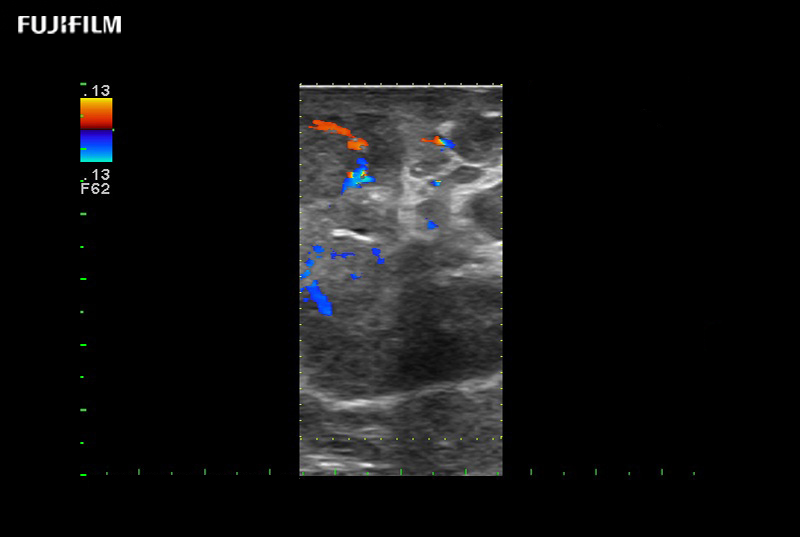

for use during robotic, laparoscopic and open surgical procedures: Tumor localization & staging, Ablation, Resection, Biopsy, Transplant, Abdominal exploration, Microsurgery

Our dedication to Robotic Surgery allows us to offer superior image quality, outstanding system reliability and intuitive use of cutting edge technology.

Linear array side-fire “T” transducer for open surgical procedures.

Exclusive linear array robotic surgery transducer.